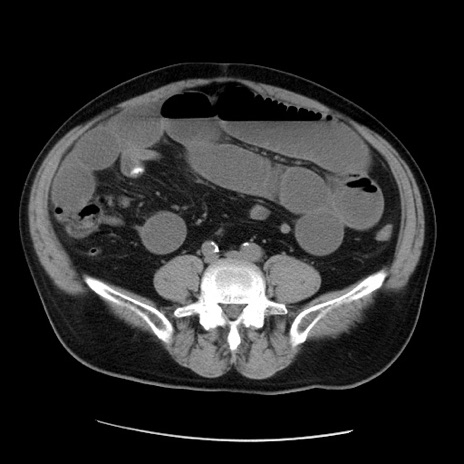

症例20(横断像)

【症例】 60歳代男性

【主訴】 腹部膨満、嘔吐

【現病歴】5日前頃より倦怠感を認め食事量減少し4日前の朝嘔吐、食事摂取困難となった。 3日前近医受診し点滴施行され整腸剤などを処方された。 当日他院を受診し、腹部膨満著明、炎症反応の上昇(CRP10.8、WBC11200)あり、紹介受診となる。

【身体所見】 意識JCS1 受け答えがはっきりしないBP 111/57mHg、 P 67bpm、、BT35.2°C、SpO2 97%(RA)、 腹部:膨隆、打診で鼓音あり、全体的に圧痛有り、腸蠕動音(-)、反跳痛ははっきりせず。

【データ】WBC 11400、CRP 14.20